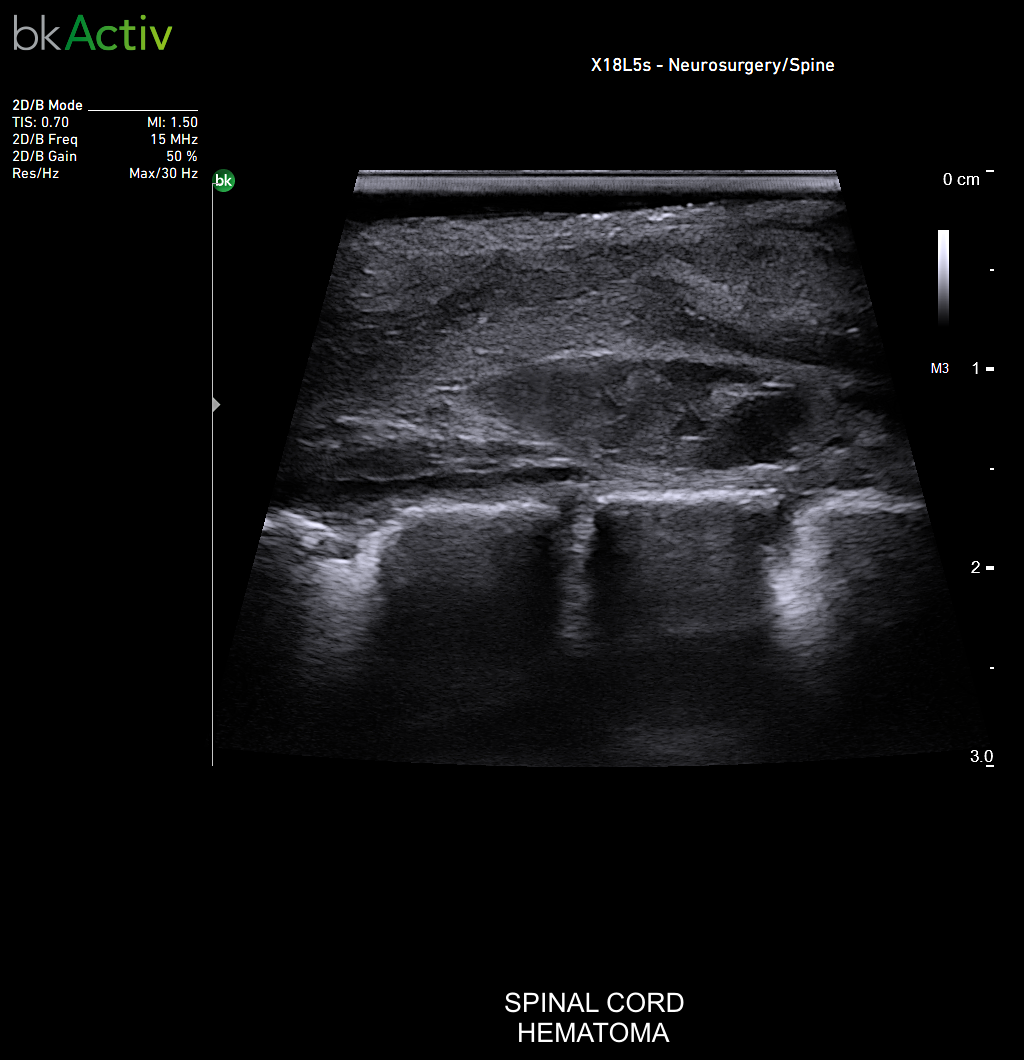

Neurosurgery and Spine

Enhanced Visualization

Improved algorithms that automatically allow uniform image resolution, greater details around lesion borders and at larger depths, and enhanced penetration, spatial resolution, and near field image quality.